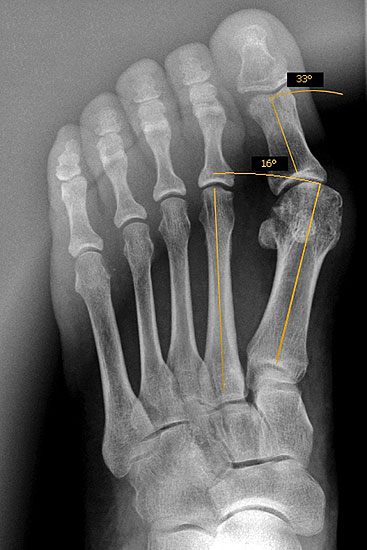

Abbildung 1

Operationsplanung anhand der Röntgenaufnahmen unter Beachtung wichtiger radiologischer Landmarks wie Intermetatarsalwinkel, Hallux valgus – Winkel, Distaler Gelenkflächenwinkel (Distal metatarsal articular angulation: DMAA), Metatarsaleindex und Sesambeinposition (Abbildung 1)

Die Chevron Osteotomie ist eine der weltweit am häufigsten angewandten Verfahren zur Korrektur einer milden bis mittelgradigen Valgusfehlstellung der Großzehe 1110121319148. Die zahlreichen Publikationen berichten über relativ verlässlich gute und reproduzierbare Ergebnisse. Durch Modifikationen in der Operationstechnik versuchten einige Autoren den Indikationsbereich auf mittelgradige bis schwerwiegende Fehlstellungen auszuweiten 121314. Die Bestimmung des Schweregrades der Fehlstellung erfolgt in erster Linie am belasteten Röntgenbild im dorsoplantaren Stahlengang (siehe Abbildung 1). An dieser Aufnahme können die wichtigsten radiologischen Vermessungen zur Operationsplanung vollzogen werden 112310121312728172930, auch wenn in einigen Studien eine große inter- und intraindividuelle Schwankungsbreite der Messergebisse dargestellt werden konnte 2930. Ebenso zeigt sich eine gewisse Varianz in der Methodik zur Bestimmung des ersten Intermetatarsalwinkels 18282931. Als Grenzwerte für einen milden bis mittelgradigen Hallux valgus werden in der Literatur in relativ weiter Übereinstimmung ein Intermetatarsalwinkel bis maximal 16° und ein Hallux valgus Winkel bis 40° genannt 688. Der DMAA ist radiologisch schwierig zu beurteilen und sollte intraoperativ bei Gelenkeröffnung inspektorisch überprüft werden 2. 2007 verglichen Trnka et al. (2007) die Ergebnisse von vier verschiedenen Nachuntersuchungsgruppen, die sich durch Modifikationen der OP Technik unterschieden: 66 Chevron Operationen von 1991 bis 1992, 100 Chevron Operationen von 1992 bis 1995, 55 Chevron Operationen von 1994 bis 1995 und 89 Chevron Operationen von 2000 bis 2002. So wurde der dorsomediale Zugang 1992 durch einen streng medialen Zugang mit L-förmiger Kapsulotomie ersetzt. 1992 wurde das laterale Release über einen dorsalen Zugang eingeführt mit Perforation der lateralen Kapsel längs zwischen Metatarsale 1 und fibularem Sesambein, sowie vertikal im Verlauf der Gelenklinie ohne Ablösung des Adduktors oder Durchtrennung des intermetatarsalen Bandes. Zwischen 1994 und 2000 wurde eine temporäre Fixation mit einem Kirschnerdraht durchgeführt. Seit 2000 wird die Osteotomie mit einer kanülierten Kompressionsschraube fixiert. Insbesondere die Einführung des lateralen Release führte zu einer signifikanten Verbesserung des Hallux valgus- und Intermetatarsalwinkels, ohne vermehrt Probleme mit einer avaskulären Nekrose des MTK 1 zu bekommen. Die Einführung einer Osteosynthese mittels Kirschnerdraht zeigte im follow up nach 34 Monaten gegenüber der lediglich manuellen Einstauchung des distalen Fragments, wie in der Originalarbeit von Austin beschrieben, eine geringere Rate an Korrekturverlusten und Dislokationen des ersten Metatarsaleköpfchens. Durch die Verwendung einer Schraube konnte das Indikationsspektrum hinsichtlich Schweregrad des Hallux valgus erweitert werden. Der Vergleich einer 2-Jahres- und eines 5-Jahres-Nachuntersuchung zeigte gegenüber der präoperativen Untersuchung eine Verbesserung des IM-Winkels von 13° auf 8° respektive 9°. Der HV-Winkel konnte von durchschnittlich 29° auf 15° respektive 16° reduziert werden. Ergebnisse, welche auch die langfristige Zuverlässigkeit der Chevron-Osteotomie in der Behandlung des milden bis mittelgradigen Hallux valgus belegen.